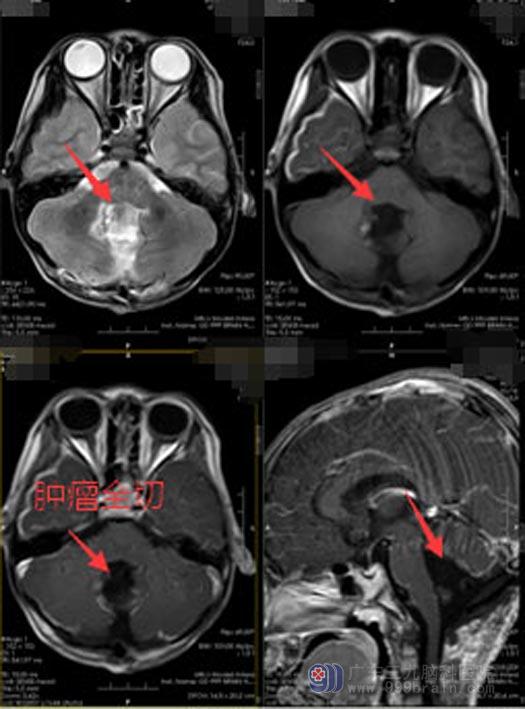

肿瘤所在的位置有丰富的血管和神经,周围毗邻脑干等重要结构,稍有不慎,会损伤脑干、血管及神经,出现严重的并发症。完善术前检查后,由医院副院长、神经外五科主任鲁明主刀在全麻下行“四脑室、小脑蚓部、右侧小脑半球占位切除术”,术中见肿瘤自四脑室侵犯至小脑蚓部及右侧小脑半球,肿瘤顺利全切,血管保护好,脑干及颅神经无损伤。术后病理提示:室管膜瘤,WHOII级,术后复查头颅MRI:肿瘤全切。

术后,明明没有出现其它并发症。眼见着宝宝手术后恢复得很好,原本无法接受事实的父母也逐渐走出了阴霾。